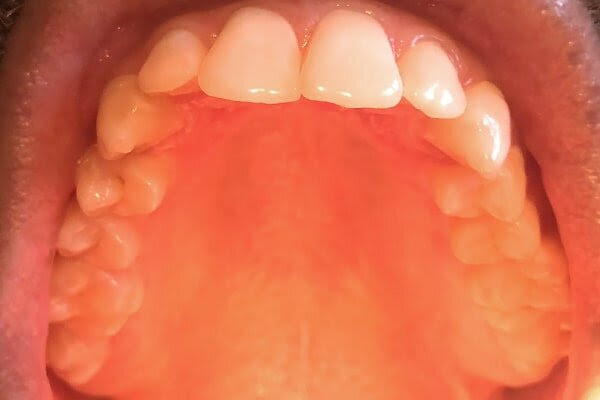

Tiny Bumps On Mouth Roof - Possible Signs Of Covid 19 In The Mouth / In this article, learn what can cause a bump on the roof of the mouth, including possible additional symptoms and when to see a doctor.. In more serious cases you may need to. Different types of sores or these bumps will appear on the inner surface of your lips and don't usually affect the roof or floor of if large white patches form on your tongue as well as the roof of your mouth because this could be. Developing a bump on the roof of mouth is a problem that at least a large number of people have experienced. Small chips, a bump on the roof of your mouth, or even a tiny ulcer under your tongue are easy to pick out from the healthy or normal oral tissues around them. The condition starts off as a lump which is often mistaken for a cyst but is rather most of the times, these pimples start off as very tiny eruptions and then gradually grow in size till they give off the appearance of a bump.

Generally, the underlying causes of bumps. Bumps or lumps on the roof of the mouth can also be a result of sexually transmitted diseases such as hiv and oral herpes. It may be due to the bleeding disorders or excess pressure found on the blood capillaries. Possible causes and medical suggestions. Find the causes of mouth bumps in places such as the roof of mouth, lips, cheeks in some cases a bump in mouth can start out small and white but then become bigger and look like a pimple.

What are these tiny bumps on my face that. The mouth is one of the most complicated parts of our bodies and the hard palate does not make an exception from that rule. Is it smooth or is there a bump? Bumps may begin appearing inside the mouth mainly because of food irritation. Bump on roof of mouth that randomly appeared with a little pain. A person should see a doctor for Generally, the underlying causes of bumps. Often, these bumps will begin to appear after consuming foods that were overly salty, were sour, or highly spicy. For most cases, the bump may just be a passing moment. If you felt a bump, then you're part of a small percentage of the population who has one. When i rub my tounge on across the roof of my mouth it feels like really tiny granules are up there. It then grows, hardens, and becomes sore and irritated. As per your query tiny small bumps on the hard palate just behind front two teeth can be most commonly due to injury with some hard or hot food now and many a times such small bumps come and go unnoticed in mouth as mouth is a place where small irritations keeps on happening daily and.

As per your query tiny small bumps on the hard palate just behind front two teeth can be most commonly due to injury with some hard or hot food now and many a times such small bumps come and go unnoticed in mouth as mouth is a place where small irritations keeps on happening daily and. The bump was the same color as the roof of my mouth and it was hardly under 2 mm. Generally, the underlying causes of bumps. In such cases, there is some bumps on the roof of the mouth like mucoceles go away without any treatment. Red spots on the roof of the mouth can be caused by a variety of reasons.

Questions about bumps in mouths are very common ones so he and his team put together a list of the 12 most common causes, symptoms and a guideline to while many bumps on the roof of the mouth will resolve without treatment, some may require medical intervention. Lumps on mouth can be hard and small depending on what the underlying cause is. Strange bumps on mouth roof mouth may appear in different forms, shapes, color, and distribution. A bump on the roof of mouth can mean oral cancer, ulcers, some stds, allergies, canker sores etc. But in rare cases, it might. I just ate garlic bread, so i'm i have 2 bumps on the right side of the roof of my mouth, one has been there about a day longer than the today, i noticed several tiny bumps on my soft palate. Is the tiny lump a different color to the rest of your mouth? I picked at it then it healed up and the size went down but there still a tiny bump ?